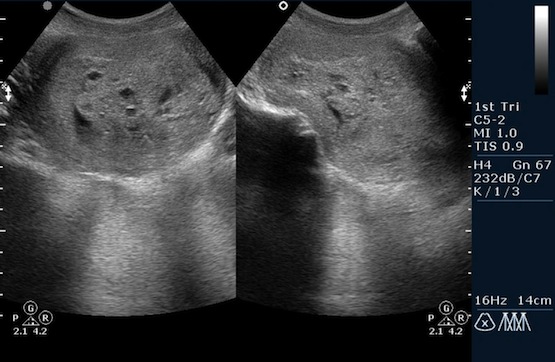

Основные методы диагностики трофобластической болезни - трансвагинальное ультразвуковое исследование, анализ крови на ХГЧ (всегда повышен), морфологическое исследование материала, полученного при диагностической лапароскопии, выскабливании, пункции метастазов, иссечении опухолей влагалища.

Как дополнительные методы диагностики применяются УЗИ органов брюшной полости, рентгенография органов грудной полости, КТ и МРТ головного мозга, тазовая ангиография.